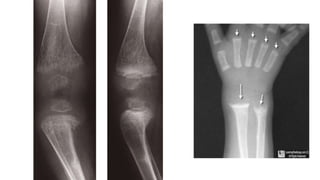

Rickets

🠶The changes are maximal where bone growth is

occurring, so they are best seen at the knees, wrists

and ankles.

🠶The zone of provisional calcification isdeficient and

the metaphyses are irregularly mineralized, widened

and cupped

🠶Widened growth plate

🠶Generalized decrease in bone density

🠶Deformities of the bones

🠶Greenstick fractures are common.